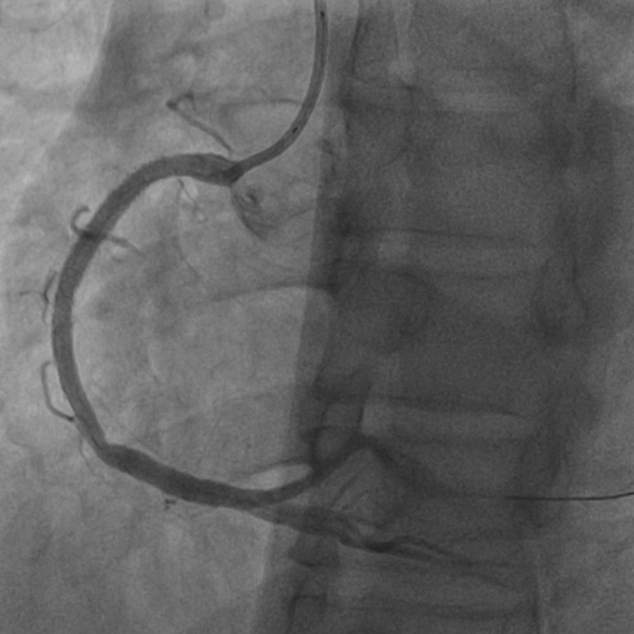

抽吸【例】量|【李】解抽吸患者获益